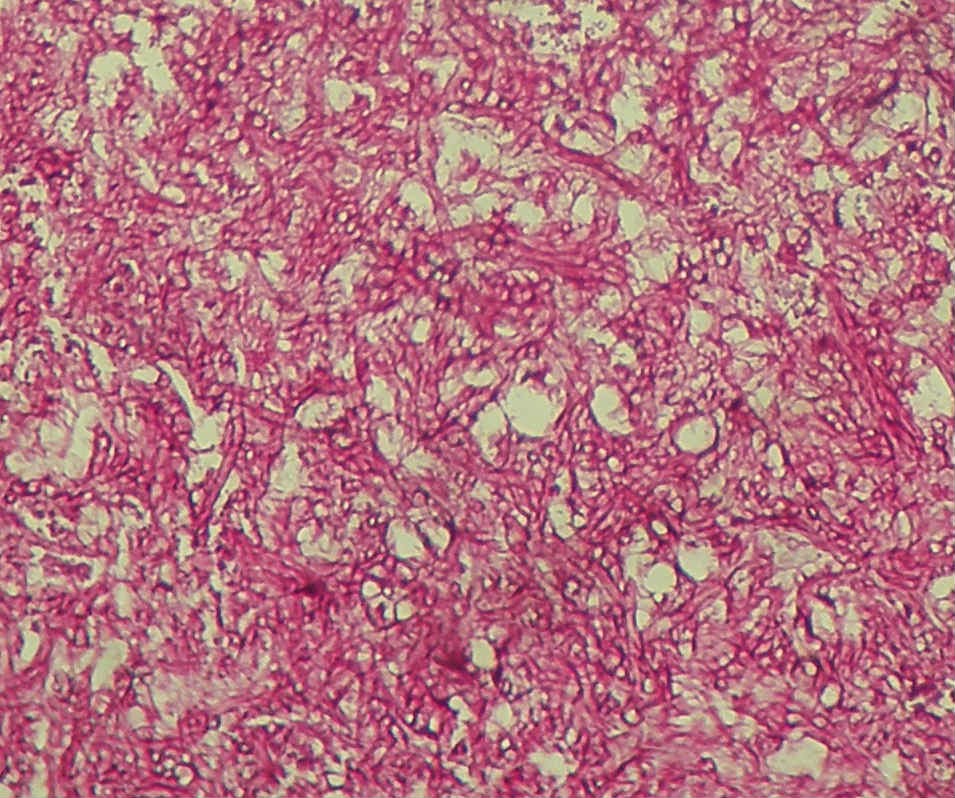

| Exame histológico de peça de biópsia: presença de hifas. |

| maior ampliação do 2º corte: enorme quantidade de hifas embora apenas uma colónia tenha sido obtida por cultura (o doente não estava à época sob qualquer tratamento antifungico) |

| massa densa de hifas pouco septadas |